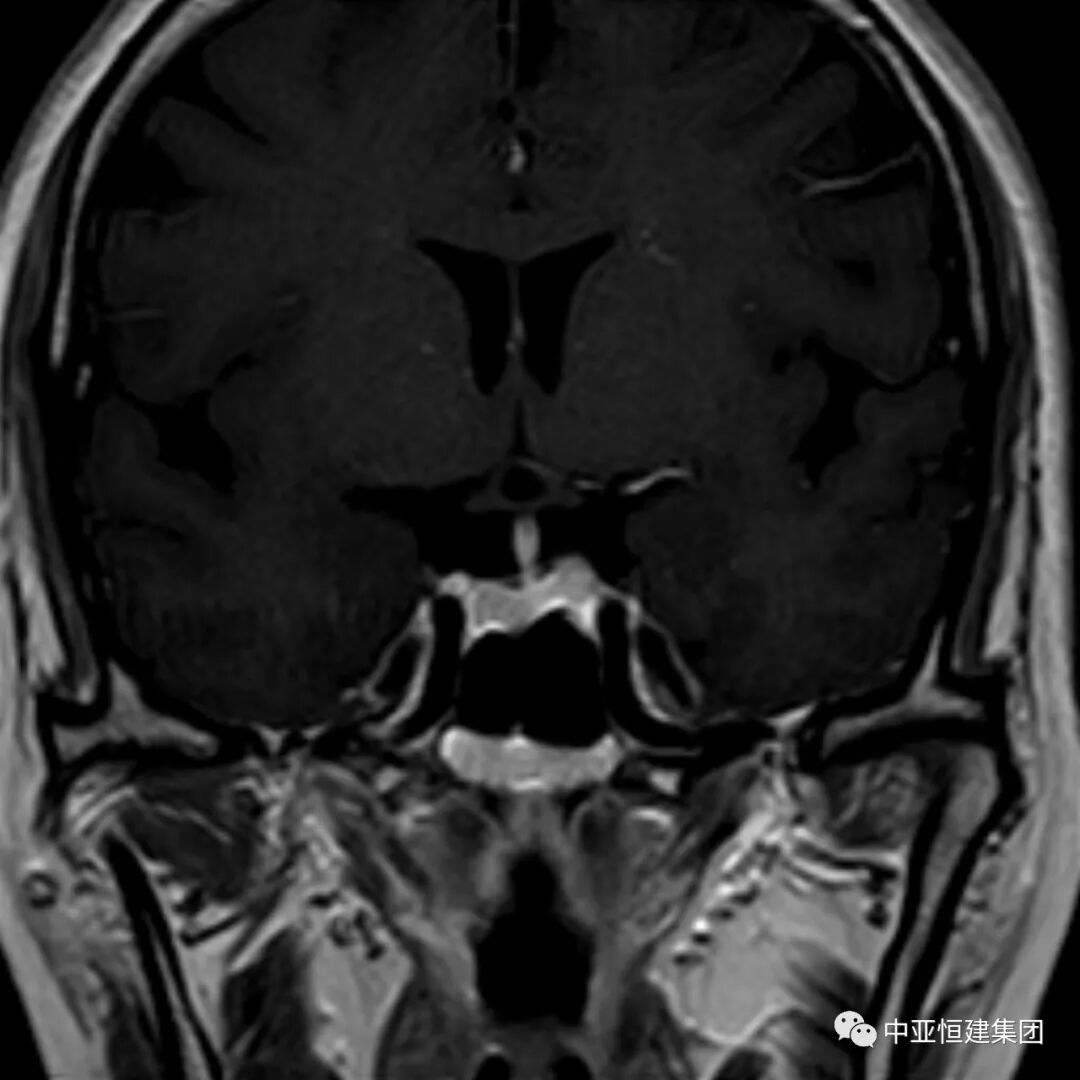

患者做头CT时未见明显异常

同一患者患者做MRI发现垂体瘤

MRI增强目前是垂体瘤诊断主要检查方式之一,垂体微腺瘤一般用冠状面和矢状面薄层,包括 T1 和 T2 图像。

T1 微腺瘤呈低信号,多位于垂体一侧,T2微腺瘤呈高信号或等信号。动态增强扫描,肿瘤信号早期低于垂体,后期高于垂体。